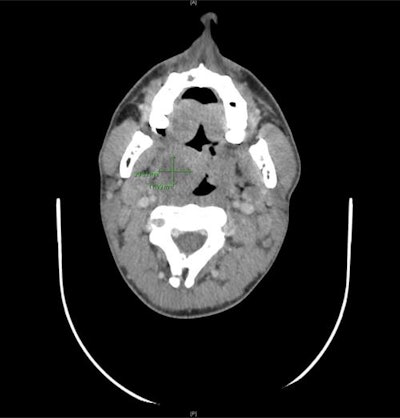

A computed tomography (CT) scan confirmed the abscess. The man was admitted to the hospital and given high-dose intravenous antibiotics and steroid therapy to manage the abscess and to limit healthcare workers' exposure to SARS-CoV-2, they wrote.

Two days after his discharge from the hospital -- 14 days from the start of his symptoms -- the patient tested negative for the novel coronavirus. The peritonsillar abscess had been treated successfully, his oral cavity was normal, and he could eat and drink without difficulty four days after his discharge. Four days later, a CT scan confirmed the complete resolution of the abscess and the antibiotics were stopped, according to the authors.